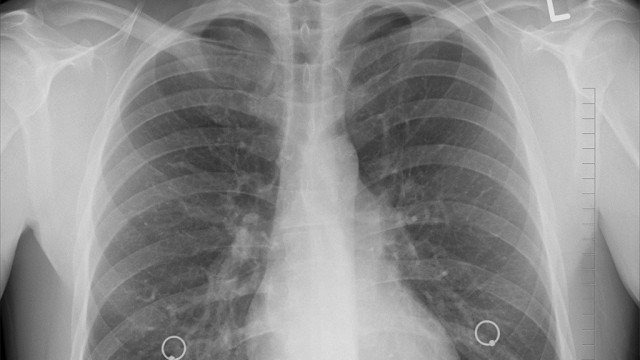

Sprawdź, czy masz zdrowe płuca

Osoby z terenów najbardziej zanieczyszczonych smogiem powinny sprawdzić stan swoich płuc. Najprostszym i...